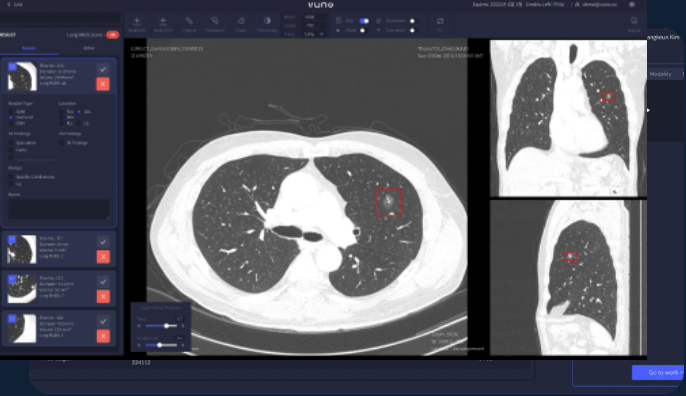

VUNO MED-LungCT AI

흉부 CT 영상을 통해 폐결절을 탐지하여 위치와 부피 정보를 제공하는 소프트웨어. 초해상도 알고리즘을 적용하여 폐결절을 탐지하며, 위치, 크기, 부피 등 폐결절의 정량화 정보를 제공합니다.